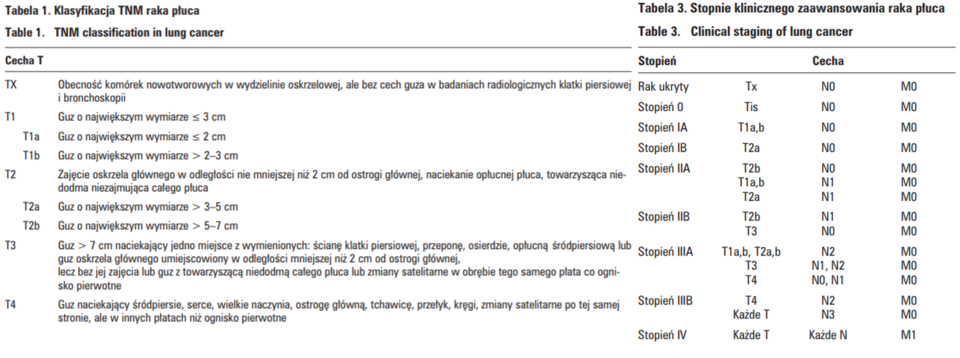

Ryc. A: 1 – rak płaskonabłonkowy, gdzie z lewej strony preparatu widać perłę keratynową. Natomiast z prawej strony cechy odróżnicowania z figurami podziałów mitotycznych. 2 – rak drobnokomórkowy z uwidocznionym wysokim stopniem anaplazji, co na obrazie manifestuje się jako komórka prawie bez cytoplazmy, ale za to z pozornie dużym jądrem.